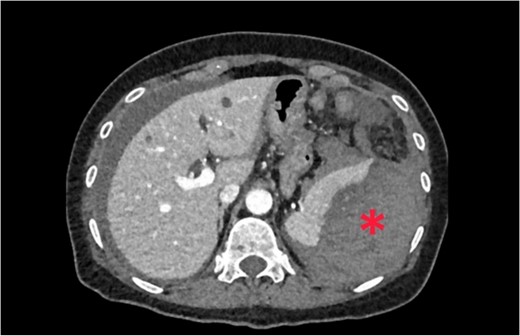

The patient was pale, hemodynamically stable, and with signs of peritoneal irritation. His hemoglobin was 15.1 g/dL. Contrast enhanced CT demonstrated 11.6 × 8.8 × 16.5 cm3 intramural hematoma in anterior stomach wall with active bleeding and hemoperitoneum (Figs 2 and 3). Exploratory laparotomy was done after optimizing the patient.